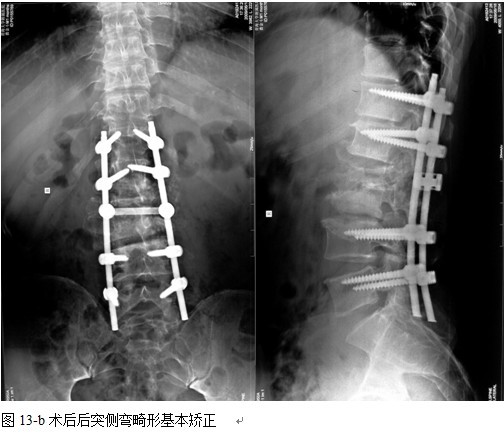

结果: 术后所有患者均显示,骨性融合, 马尾神经损伤的患者均基本恢复正常,术后后凸畸形平均矫正90%以上, 3-49个月的随访,后凸角度平均丢失4.2°。

本组手术用时间3~4h , 平均3.5h 。术中出血300~500ml , 平均约350ml 。术后症状完全缓解,无神经功能障碍加重等并发症,1例营养差的老年患者伤口出现窦道,1例因肝功能差,术后未口服抗痨药,伤口出现窦道,经换药后二期愈合,其余病例伤口均一期愈合。马尾神经受损的患者术后基本恢复正常。术后一周后凸角平均 5.4°后凸畸形平均矫正90%以上, 最终后凸角平均8.3°,后凸角度平均丢失4.2°。随访3个月有87%(40/46)有骨痂形成,6个月91.3%(42/46)明显骨性愈合(见图),其余4例9-12个月内愈合,随访时间3-32个月,平均11个月,46例患者中2例在术后2个月和3个月时背部形成脓肿,换药后治愈。2例出院1月后并发结核性脑膜炎,治疗后好转。1例因椎弓根钉偏外,刺激神经根,5个月后从侧方脱出,疼痛加重,因前后路植骨完全愈合,取出后症状完全缓解。

中国学者金大地[22]等采用一期前路病灶清除植骨前路钢板固定治疗腰椎结核,平均18°的后凸畸形得以矫正,Mukhtar[23] AM等采用前路病灶清除植骨分期或同期后路固定治疗腰椎结核22例,术后后凸畸形矫正度数平均为27°。从我们的随访结果看,术后后凸畸形平均矫正度数为26.9°,后凸畸形平均矫正90%以上, 6个月-49个月后随访,后凸角度平均丢失4.2°。本术式也适用于结核所引起的弹性差的后凸畸形,对于病灶纤维化或骨化的非弹性后凸畸形,后路固定后,先行前路病灶、纤维化或骨化切除、松解,逐步刮除病灶、逐步撑开,达到畸形矫正和植骨的目的。